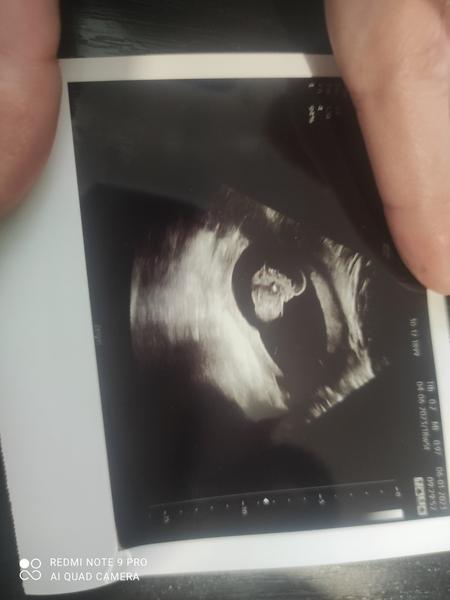

Je to holka nebo kluk? Nejistota po vyšetření ultrazvukem.

ahoj holky co vidíte jsem v 20 tt. v 16 týdnů mi můj gynekolog rekl vidí na 85 procent kluka a dnes gynekolozka řekla ze vidí zase holku dneska to je 20 týden

@baby03 tak za mě je tohle tedy utz snímek holčičky 🙂

Kluci to mají spise jako doslova mezi nozickama tohle mi přijde jako přímo v rozkroku, u syna jsem měla pindika na fotce a byly tam stehynka uprostřed pindik mezi stehýnkama a tam kousek odd prdelky měl koulicky takže tohle spis holka